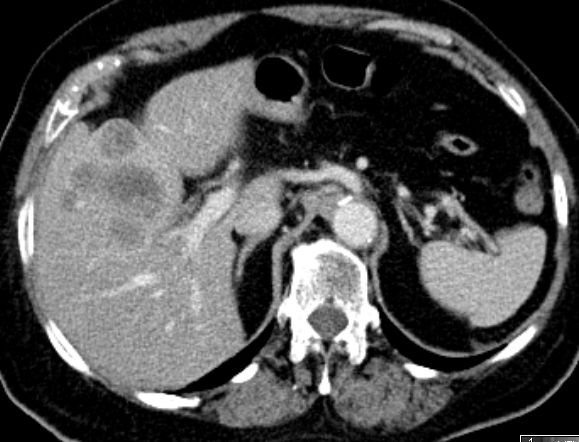

| Klinik | 91-jährige Frau mit Gallenblasen - Hydrops. Histologisch schlecht differenziertes Adenokarzinom. Ductus cysticus tumorös verdickt.![]() |

Lebermetastasen.![]() | ||